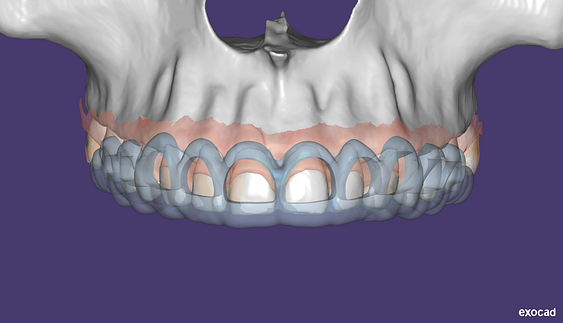

- CBCT segmentation

STLs of upper and lower jaws imported into Modjaw for TMJ analysis in jaw motion. this is made possible by CBCT segmentation using Diagnocat.

The surgical crown lengthening guide was made with the aid of maxilla STL to visualize crestal bone level. Again thanks to CBCT segmentation by Diagnocat.

These can then be individually exported via the software by generating STL files from CBCT dicom data. This can be used in other dental software. Jaw STLs can be used in Modjaw (jaw motion capture) for TMJ analysis, for example. As well as in exocad to help visualize the jaws for surgical planning or guide creation.